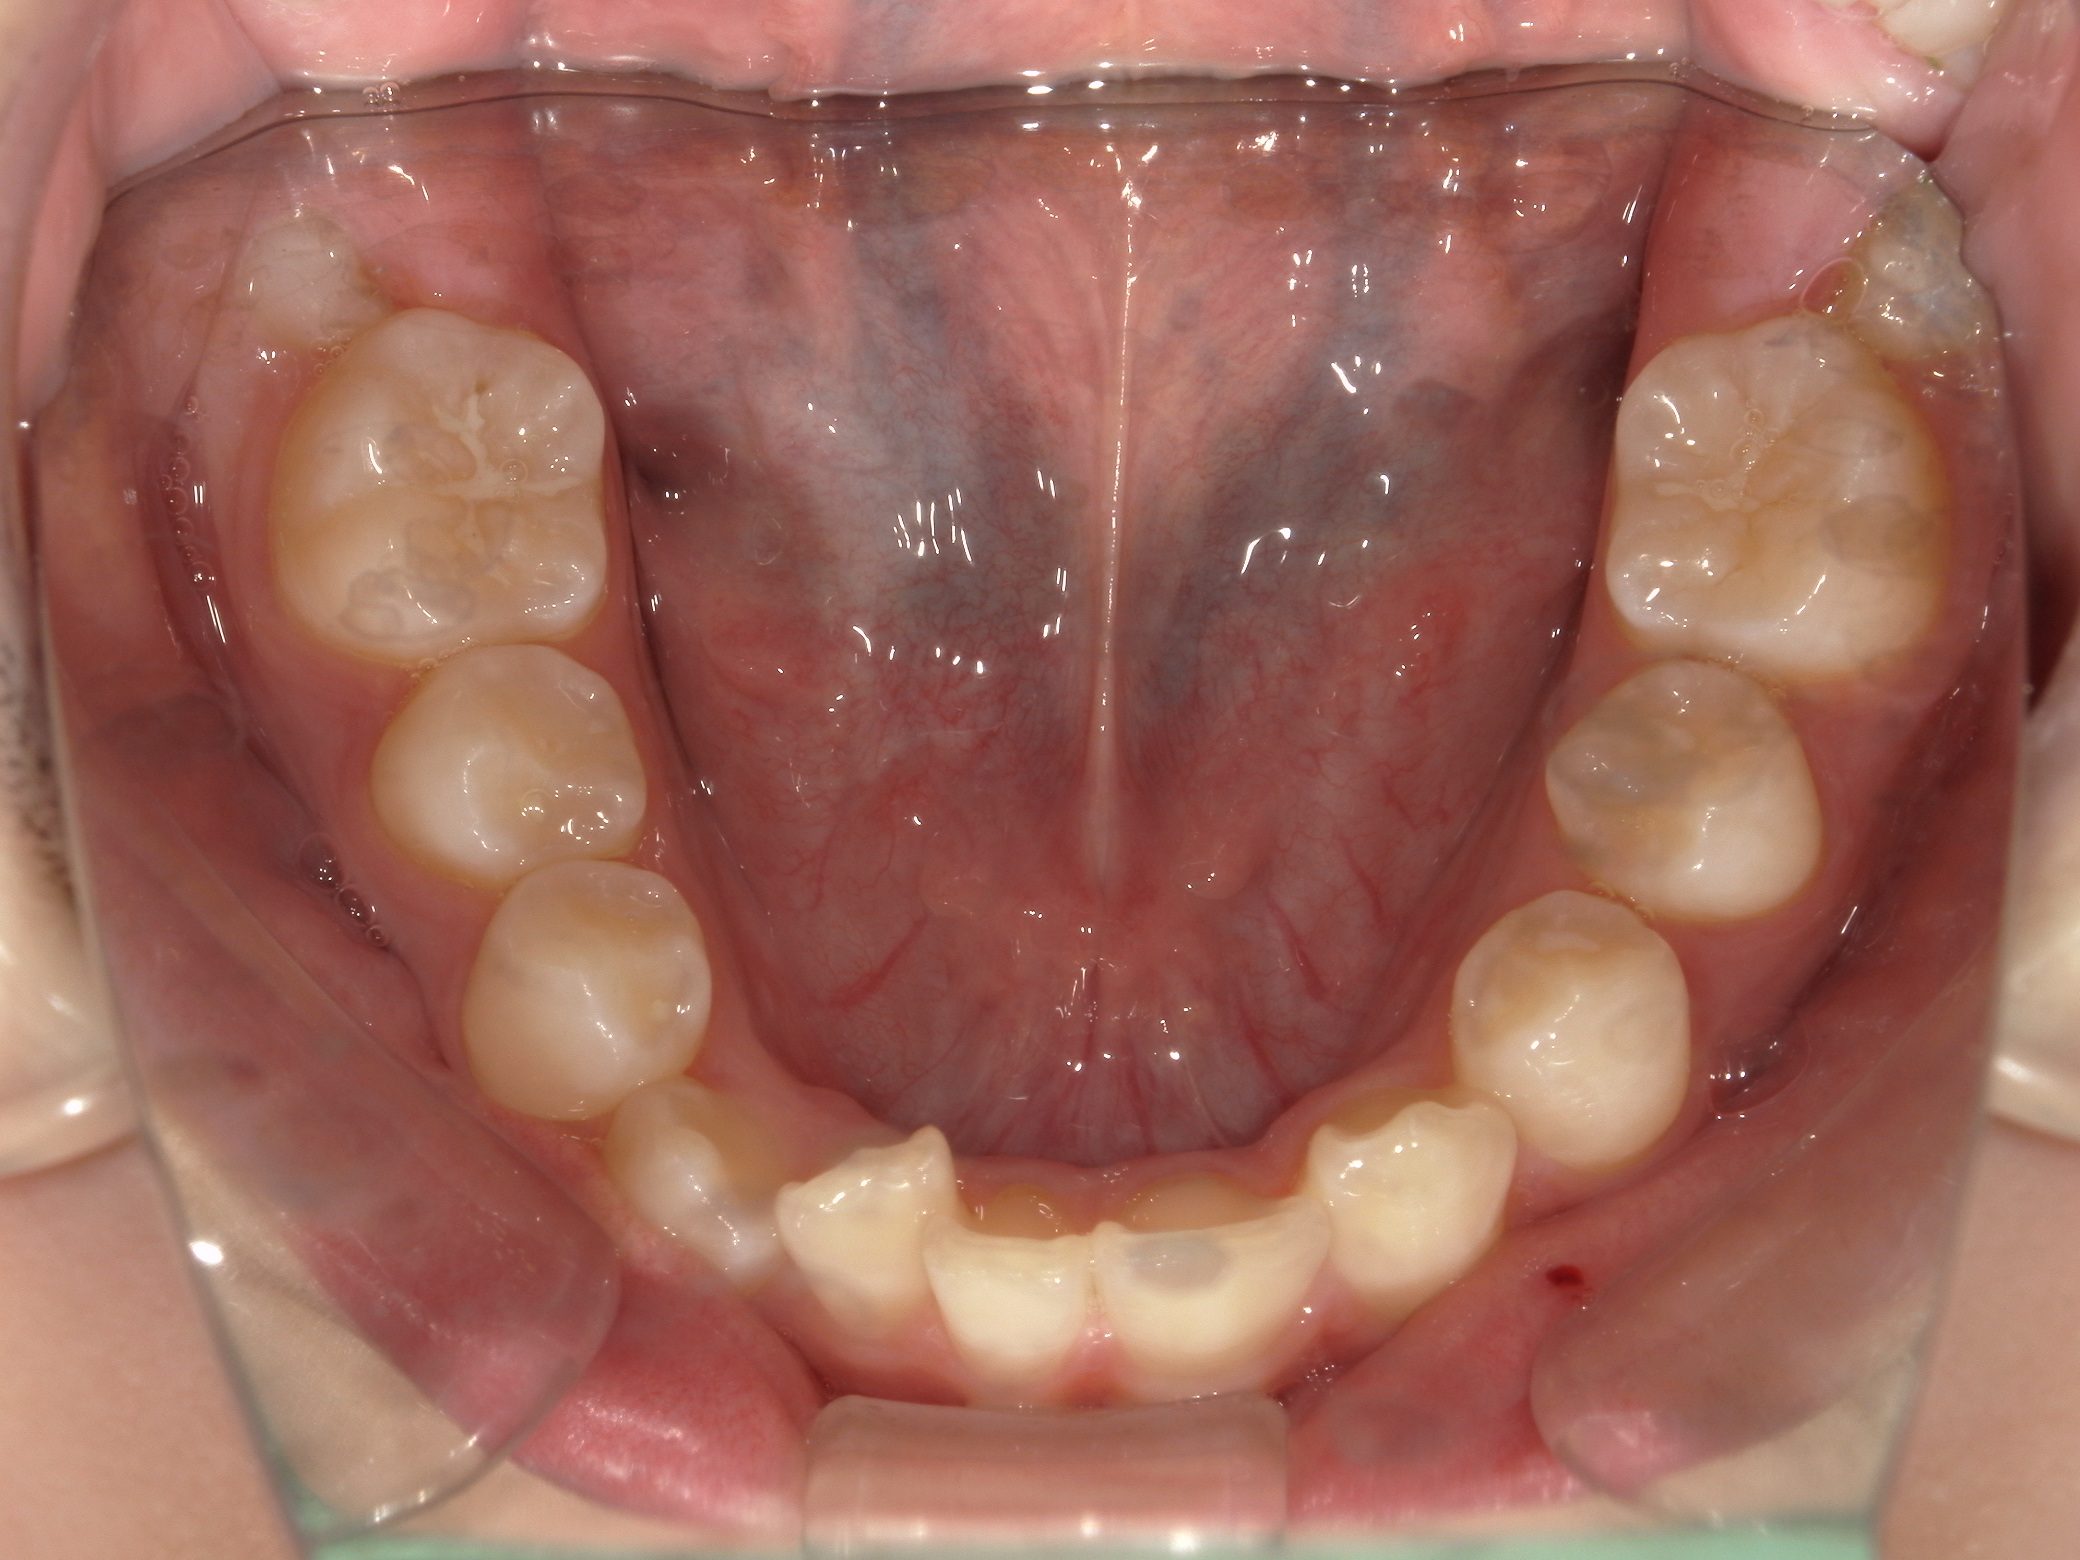

【中学生】インビザラインフル 先天欠損歯あり 叢生(でこぼこ) を改善

中学生以降

インビザライン フル

でこぼこ

過蓋咬合

非抜歯

2期治療のみ

Before

After

治療期間

10か月年

治療開始

14歳

種類

インビザライン矯正

使用装置

インビザラインフル

コメント

下顎の前歯が生まれつき1本少ないので

過蓋咬合になりやすい歯並びです

咬み合わせの深さを改善することと

下顎の叢生(でこぼこ)を改善すること

奥歯の咬み合わせを 歯が1本少なくても しっかり作り上げること

この3つを実現して治しています。